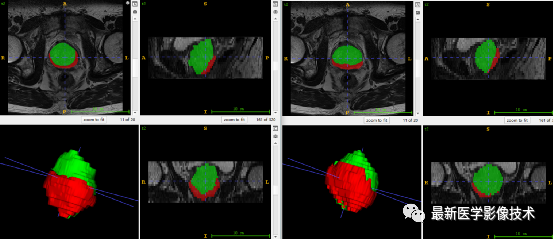

5、验证集分割结果

左边是金标准结果,右边是网络预测结果。